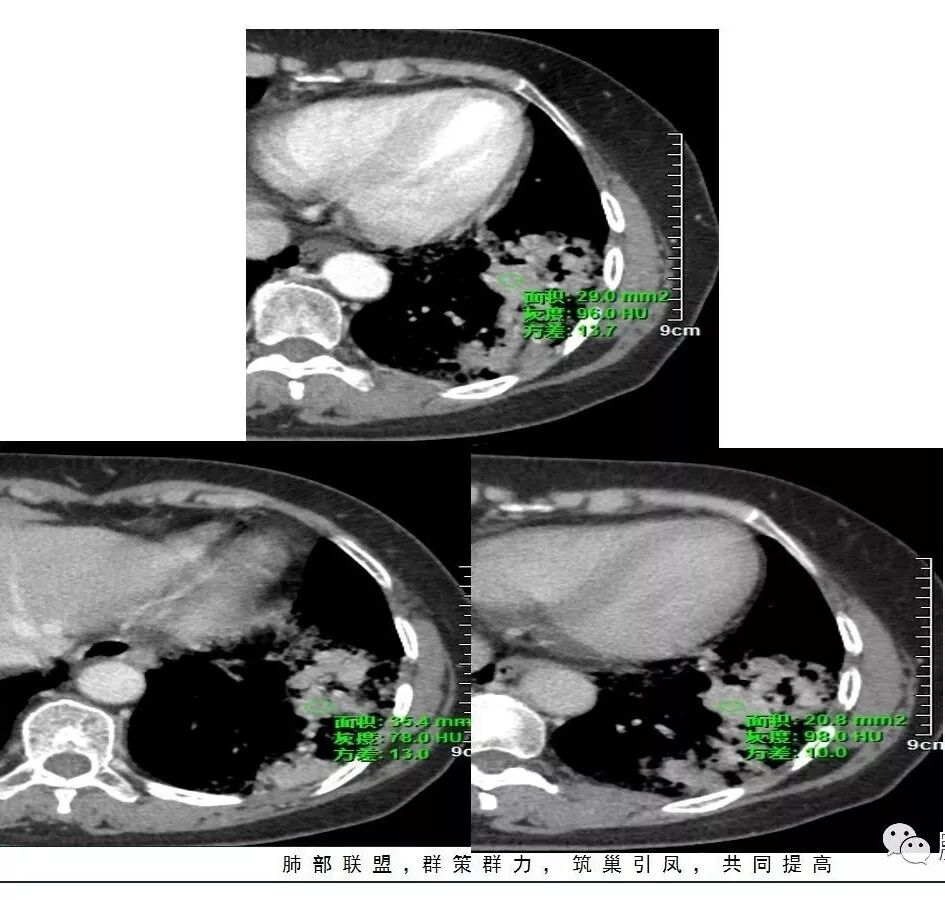

这是老问题:1、肺门区软组织密度影较弥漫;我们常规鉴别的就是结核?鳞癌?既往我们群里基本这两方向。2、弥漫的淋巴结钙化,加上马赛克灌注。马赛克灌注的原因是两个,一个是肺动脉的,一个就是小气道的问题。我们看增强的区域,没有看到栓塞,所以我倾向于小气道的问题,就是弥漫气道病变,慢性气道病变要考虑。我怀疑有没有淀粉样变性累及气道壁改变的可能。淀粉样变性是一个继发性病变,结核也可以,粉尘也可以。

实变部分强化很明显,怎么解释合理呢

肉芽肿期强化明显

肉芽肿是一个病理的概念,是炎症后期的修复,它的本质其实是迟发型过敏反应引起的炎症,在免疫应答中主要是一些巨噬细胞、上皮细胞来起作用,但是里面有非常丰富的毛细血管,所以这类病变强化很明显,影像上一般是结节状、团块状、大片状,整体有膨隆,边缘也有收缩,肉芽肿是一大类,影像有时很难区分,尘肺、结节病、淋巴瘤样肉芽肿都可以。常见的是炎性的,多见于结核,细菌性感染后期引起的类似op样,影像统称肉芽肿类病变,鉴别炎性还是恶性,要根据边缘、形态、周围结构及内部坏死情况。

今天这个病例有个明显的支气管狭窄,我倾向炎性,主要是和钙化淋巴结相关的,可能是继发的淀粉样变性。到底是什么感染,结核还是其他。我想看看复查后这个淋巴结,有没有突入到支气管腔内,如果有,他是继发于炎症的(比如中叶综合征,就是周围淋巴结压迫支气管,因为钙化淋巴结比较硬,支气管壁扛不住压力,突入支气管腔内,导致管腔狭窄,我们也称为结石征),如果没有,就和淋巴结关系不密切。之前有一例淀粉样变性的,淋巴结弥漫钙化,一种罕见的浆细胞型的CD。

3.病灶强化比较明显。